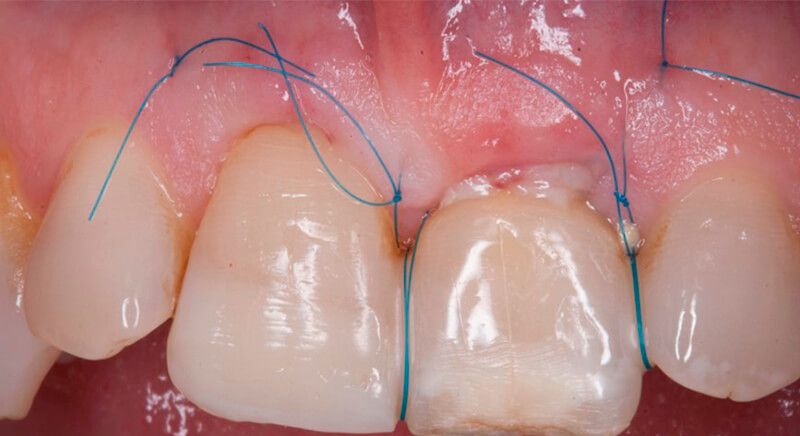

Once the hard and soft tissues had healed, 6 months after the surgery, a good volume remained in the vestibular area. It was then that we could consider an implant, using guided surgery to ensure it was placed in the correct three-dimensional position.

The socket was filled with a xenograft after the extraction and a graft of connective tissue was placed in the vestibular area of the two upper central incisors.

The tissue with epithelium was taken from the palate and de-epithelialized outside of the mouth. This obtains a lamina propria graft with better density and quality than if it were obtained with a single incision to the palate.